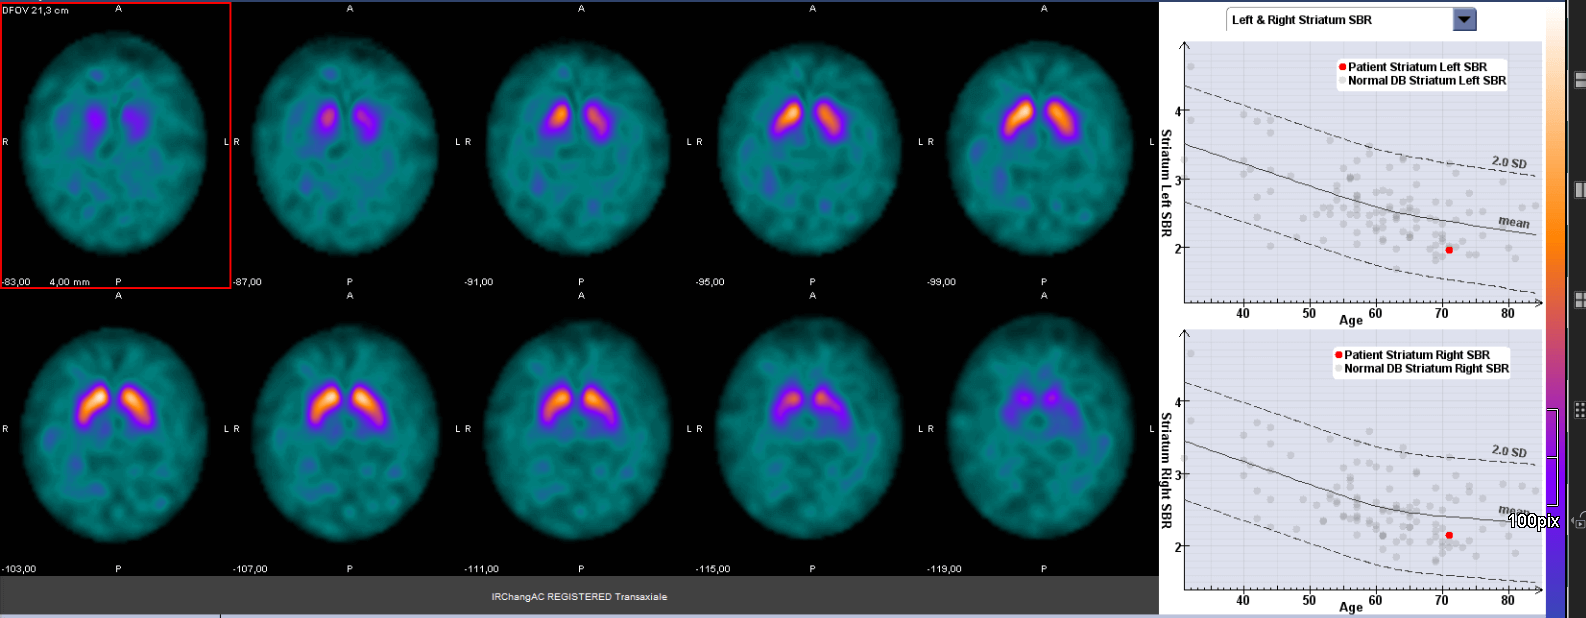

Eine Hirnszintigrafie (DAT-Scan) ist eine nuklearmedizinische Untersuchung, um die Funktionsfähigkeit bestimmter Nervenverbindungen im Gehirn zu überprüfen. Es handelt sich um Hirnrezeptoren, sogenannte Dopamin-Transporter. Diese werden bildlich dargestellt. Je mehr dieser Hirnrezeptoren vorhanden sind, desto mehr von dieser Substanz reichert sich im Gehirn an. So führen wir im Rahmen der Parkinson-Diagnostik eine spezielle Szintigrafie (Bildgebung) des Gehirns durch.

Bei der Hirnszintigrafie überprüfen wir die Funktionsfähigkeit besonderer Nervenbindungen in einem bestimmten Hirnareal, der Substantia nigra. Ziel dieser Untersuchung ist es, Informationen über die Ursache einer Bewegungsstörung zu bekommen. Da bei Erkrankungen wie dem Morbus Parkinson bestimmte, hochspezialisierte Nervenzellen zugrunde liegen, bei anderen Erkrankungen dagegen nicht, kann man die Krankheiten anhand der Hirnszintigrafie voneinander abgrenzen. Hierdurch kann der behandelnde Arzt (Neurologe) besser festlegen, welche Medikamente zur Behandlung der Erkrankung eingesetzt werden sollen.

Die Hirnszintigrafie dauert circa 60 Minuten. Wir führen die Aufnahmen des Kopfes mit einer Gammakamera durch. Dabei drehen sich die beiden Aufnahmeköpfe der Kamera langsam um Ihren Kopf und nehmen die entsprechenden Bilder auf. Wichtig ist, dass Sie ruhig und entspannt liegen, damit die Aufnahmen nicht verwackeln. Die Auswertung der Aufnahmen erfolgt mit einem speziellen Auswerteprogramm. Daher können wir Ihnen das Ergebnis der Untersuchung nicht gleich im Anschluss mitteilen. Wir werten alle Daten am Aufnahmetag aus. Der Arztbrief mit den Ergebnissen der Hirnszintigrafie schicken wir am nächsten Arbeitstag an den Zuweiser. Wir bitten darum, mit dem Zuweiser einen Termin zu vereinbaren, um das Untersuchungsergebnis und die Therapie zu besprechen.